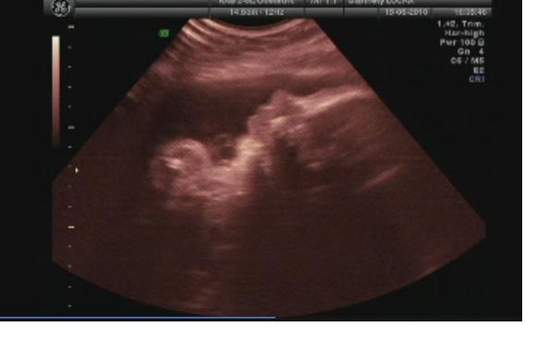

i gratulacje dla rodzicow!!!faktycznie sie synus wbil rowniutko w czasie ;-)